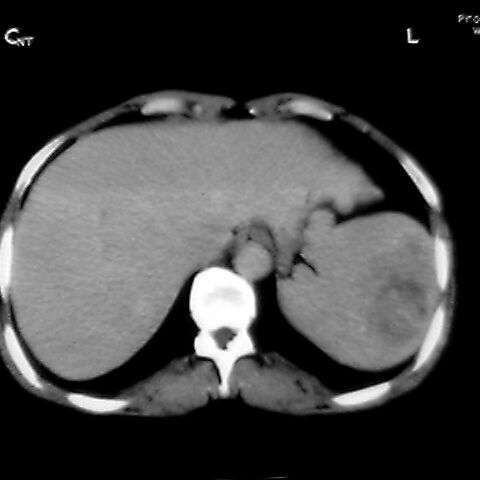

标题: [原创]CT4167脾占位。请大家帮忙会诊。

女 48岁 食道癌术前体检发现脾占位。

脾胀内部巨大低密度肿块,边界清或不清,中心坏死,轻度增强,内见散在钙化,结合食道癌病史多考虑:转移癌.

脾脏低密度灶伴钙化,增强化明显,中心见液化坏死灶,强化延时明显。考虑血管瘤。转移瘤待排。